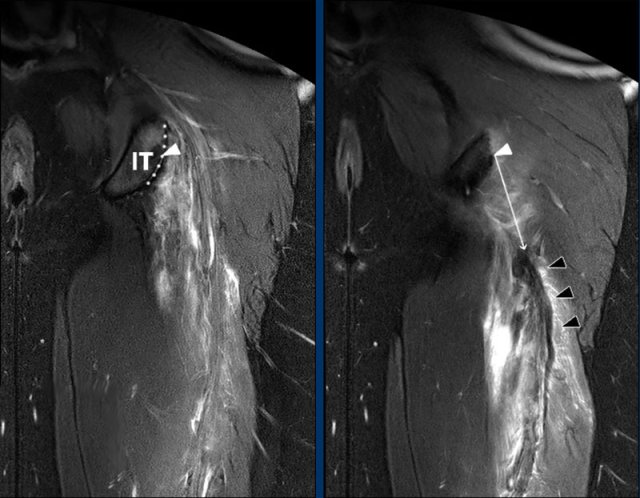

Direct measurement of retraction

The most reliable method to quantify retraction is the ‘direct measurement’ on a coronal fluid-sensitive sequence.

First, the point representing the center (white triangle) of the proximal hamstring complex origin on the upper region (dotted line) of the ischial tuberosity (IT) is determined.

From this point, the direct (ie, shortest) distance (white arrow) to the most proximal part of the hypointense tendon stump (black triangles) is measured (in cm).

Note that determining the anatomic landmarks is done on different images within one MRI sequence.